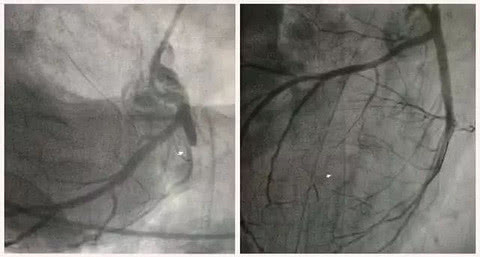

“像他这种情况,如果处理不及时,极有可能出现生命危险。”医院心内科团队阮宏标、叶如剑等专家赶到医院会诊,准备为李先生行“冠脉造影+急诊PCI”手术治疗。

16:42病人进入导管室。医生使用导丝通过极其狭窄的病变处,再用球囊扩张血管、开通血流,并摆放支架,才解决了差点要了李先生性命的“犯罪血管”。李先生胸闷胸痛症状也得到了明显的改善。